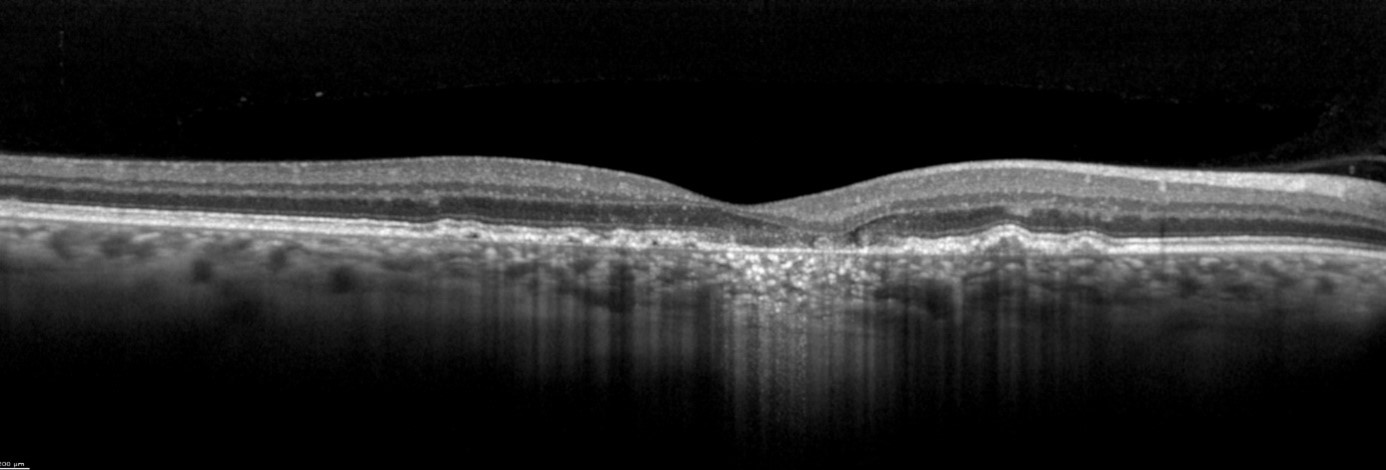

The vitality of the RPE is not the only factor of importance in GA. One of the advantages of OCT imaging is the three-dimensional cross-sectional imaging, which allows detailed viewing of fine structures. Individual retinal layers can be visualized to assess the RPE and photoreceptors. OCT is also a useful method to examine areas surrounding atrophy, such as discontinuous outer bands (external limiting membrane, ellipsoid zone, and RPE, as well as "outer retinal tubulations" (ORT)). In addition to fundoscopy and fluorescein angiography, high-resolution SD-OCT should primarily be used for diagnosis and follow-up of active choroidal neovascularization (CNV). according to professional associations.

Image 2: SPECTRALIS high-resolution OCT image courtesy of Dr. Rosa Dolz-Marco, Valencia, Spain

The transverse section or en-face OCT image option provides a unique visualization of RPE and photoreceptor structure, adding complementary information relating to the distribution of pathological change within the posterior segment. One characteristic of GA is choroidal hypertransmission defects, a “window” defect through the RPE associated with nascent GA (nGA) and cRORA, providing a complementary alternative to autofluorescence images.